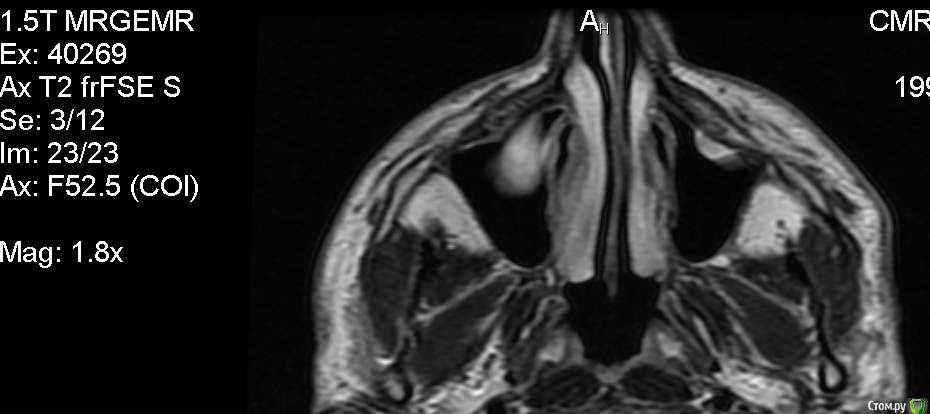

Сделал МРТ головного мозга с контрастом и без, в мозге патологий не выявлено, по заключению киста верхечюлестной правой пазухи. МРТ делал по причине непонятного тянущего ощущения в правой половине головы, не боль, просто стал себя чувствовать не как обычно. Ходил к лору, еле убедил вставить диск и посмотреть снимки, на, что получил ответ, что это от зубов и дорога моя к стоматологу. Высказала мнение, что достаточно вылечить зубы и корни, а кисту можно не трогать. Хочу получить мнение со стороны, и примерную тактику лечения в таких случаях.

Анамнез: уже 1.5 года немного воспалены/набухшие (гингивит?) края десны на верхней челюсти у 8,7,6,5 зуба, больше у 7 и 6. (Небольшая кровоточивость при чистки) На ощупь десны не болят, и зубы тоже. В них нет пломб. После заключения стал ощущать еле заметную тяжесть над перечисленными зубами.

Прилагаю фото снимков.